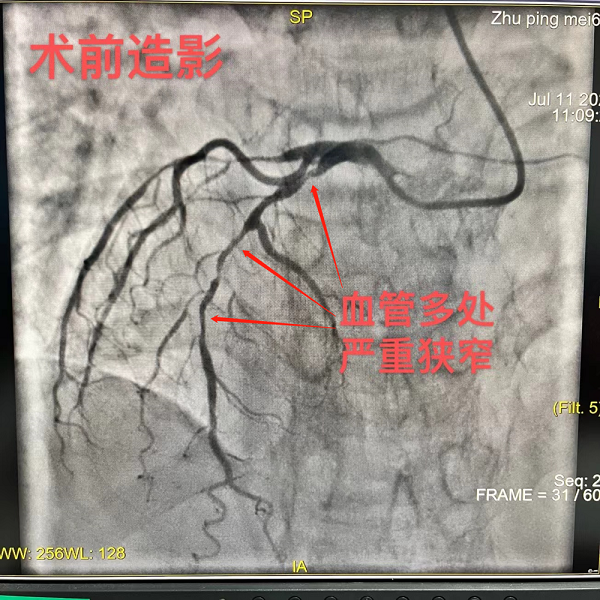

在进行心电图、心肌酶谱等一系列检查项目后,胸痛中心医生立即通知她办理入院进行治疗。心内科团队考虑朱阿姨胸痛原因为急性非ST段抬高型心肌梗死,即冠状动脉粥样硬化斑块破裂引起心肌缺血性损害,经过详细的评估,需要在24小时行介入手术开通血管,当日上午,心内科介入团队决定为朱阿姨进行冠状动脉造影和冠状动脉支架植入术(PCI)。

相对而言,为“镜面人”手术,对医生的操作要求更高,一般来说,人的心脏在左侧,而朱阿姨的心脏在右侧,因此在介入导管操作过程中,医生需要利用反向思维,将常规的左侧解剖要变成右侧解剖,采用镜面式探查血管开口等方式来完成,因而大大增加了难度。

随着导管到位、导丝通过严重狭窄的血管、球囊扩张钙化斑块之后,便可以放心处理问题了——进行冠状动脉支架植入。